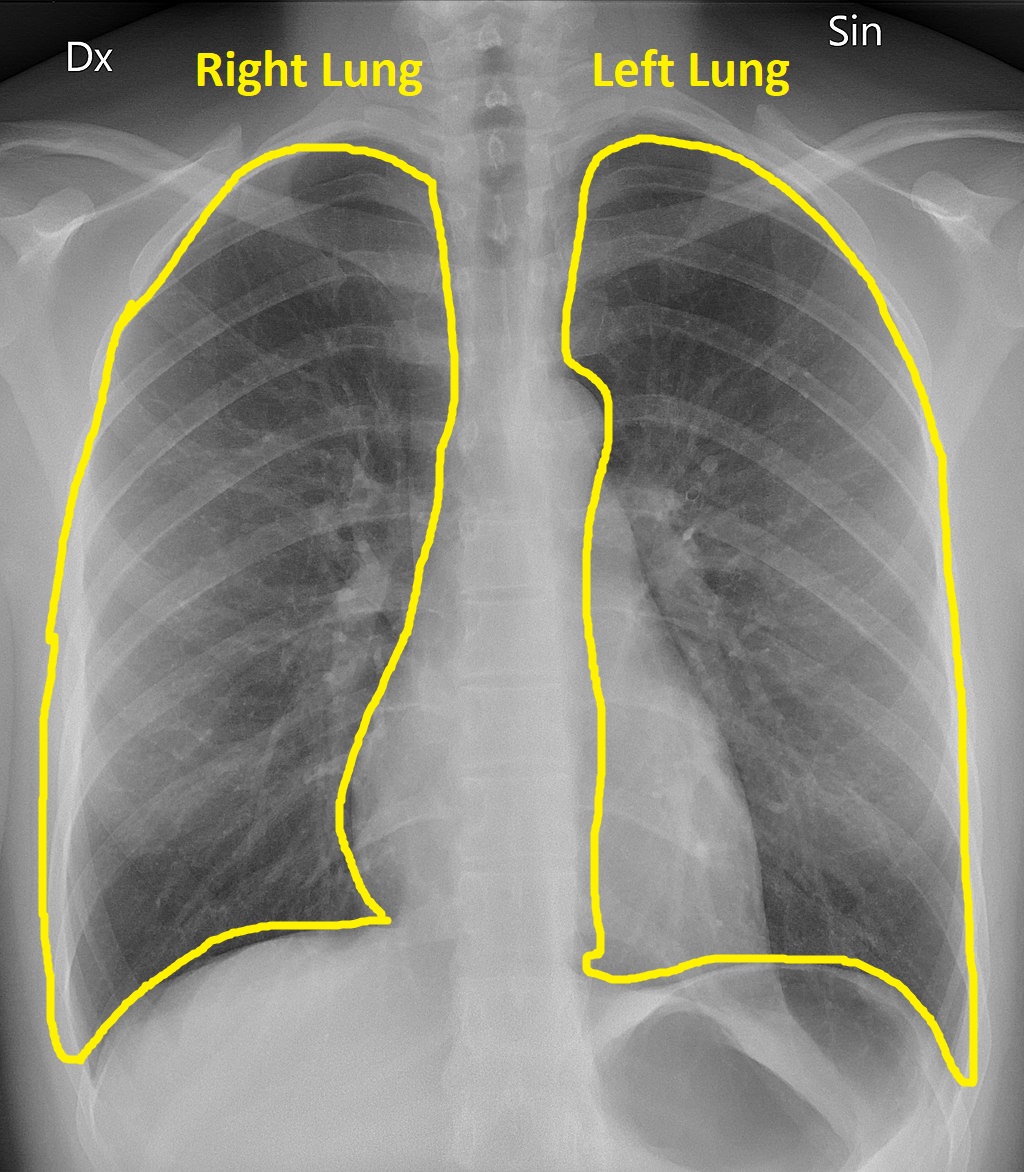

Lungs

Here I’ve outlined the lungs in yellow. You can see that part of the left lung overlaps the heart. The lungs are the darkest part of the chest x-ray because they are the least dense.